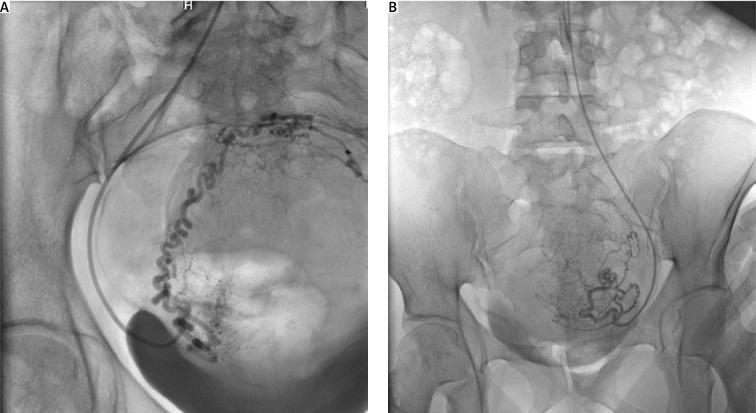

Uterine artery embolization (UAE) is a minimally invasive method that has been proven to be an effective alternative to hysterectomy and myomectomy for the treatment of symptomatic fibroids, though its impact on fertility and obstetric outcomes remains controversial. This case report presents a 31-year-old nulliparous woman with a history of fibroid-enlarged uterus (about the size of a 16-20-week pregnancy), who underwent UAE treatment, became pregnant, and delivered a healthy child by cesarean section. At the age of 35, a second UAE was performed due to recurrence of symptoms, followed by a successful conception and delivery of a second child. This report explores the clinical course, management strategies and the role of a multidisciplinary approach in achieving successful outcomes. Although substantial evidence has accumulated in the literature about the safety and effectiveness of UAE as a non-surgical option for uterine fibroids treatment, this procedure still raises questions about its impact on future fertility and obstetric outcomes, including the risk of miscarriage, placenta previa, and preterm delivery. Uterine artery embolization is a promising minimally invasive alternative to myomectomy for women with fibroids who want to preserve their fertility. The present case demonstrates that successful conception and childbirth are possible when patients undergo close follow-up and individualized management.

子宫动脉栓塞术(UAE)是一种微创方法,已被证明是治疗有症状子宫肌瘤的子宫切除术和肌瘤切除术的有效替代方法,尽管其对生育能力和产科结局的影响仍存在争议。本病例报告介绍了一名31岁未生育的女性,其有子宫肌瘤导致子宫增大(约16 - 20周妊娠大小)的病史,接受了UAE治疗,随后怀孕并通过剖宫产分娩了一个健康的婴儿。35岁时,由于症状复发进行了第二次UAE,之后成功受孕并分娩了第二个孩子。本报告探讨了临床过程、管理策略以及多学科方法在取得成功结局中的作用。尽管文献中已积累了大量关于UAE作为子宫肌瘤非手术治疗选择的安全性和有效性的证据,但该手术仍引发了关于其对未来生育能力和产科结局影响的问题,包括流产、前置胎盘和早产风险。对于希望保留生育能力的子宫肌瘤女性,子宫动脉栓塞术是一种有前景的替代肌瘤切除术的微创方法。本病例表明,当患者接受密切随访和个体化管理时,成功受孕和分娩是可能的。